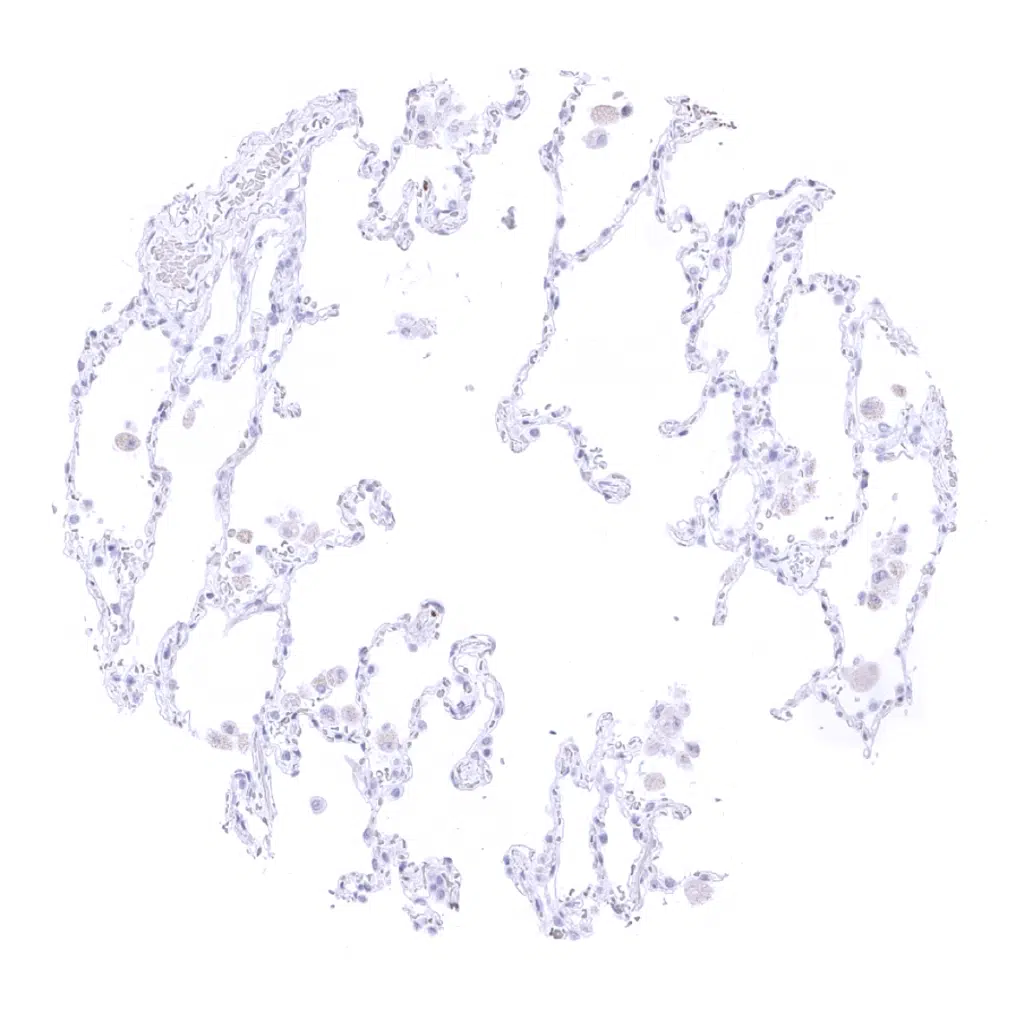

Desmin antibody [MSVA-651M] HistoMAX

Lung